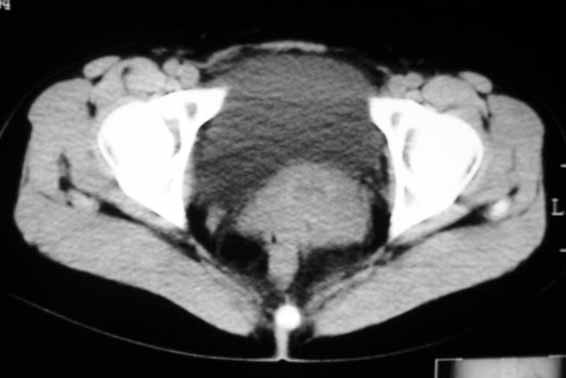

标题: CT8123:女46岁,左下腹胀痛不适1月,以前曾有月经过多史,现已 [打印本页]

标题: CT8123:女46岁,左下腹胀痛不适1月,以前曾有月经过多史,现已

子宫增大密度较均匀,考虑子宫肌瘤,不强化不好说

考虑子宫肌瘤(变性)或子宫腺肌病,不排除内膜ca可能,不增强建议结合mri或b超检查。

子宫增大密度较均匀,考虑子宫肌瘤可能性大,

建议结合b超